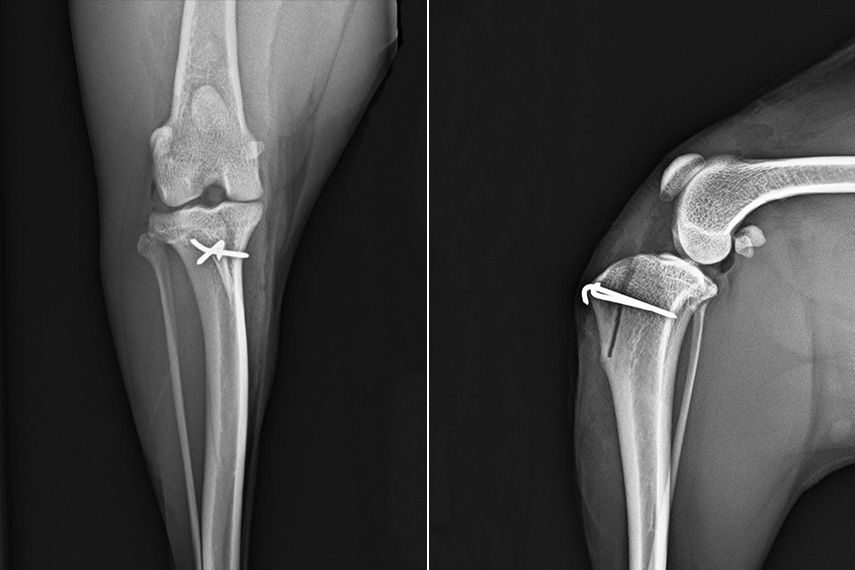

• Versetzung der sogenannten Tuberositas tibiae (der Knochenvorsprung am Unterschenkel, an dem die Sehne der Kniescheibe, die sog. „Patellarsehne“ ansetzt)

Sollte Ihr Hund über eine sehr deutliche Fehlstellung eines Knochens verfügen, wird es in einigen Fällen nötig werden, diese durch eine sogenannte Osteotomie zu beheben. Hierbei wird der Knochen durchgesägt, meist auch ein kleiner Keil entfernt, und der Knochen dadurch wieder gerade gerichtet. Im Anschluss wird er mit einer Platte wie nach einer Fraktur wieder fixiert. In einigen Fällen ist diese Fehlstellung die alleinige Ursache und ein Geraderichten des Knochens reicht bereits aus, um die Patella wieder gerade in ihrem Sulcus laufen zu lassen.

Patellaluxation post operativ